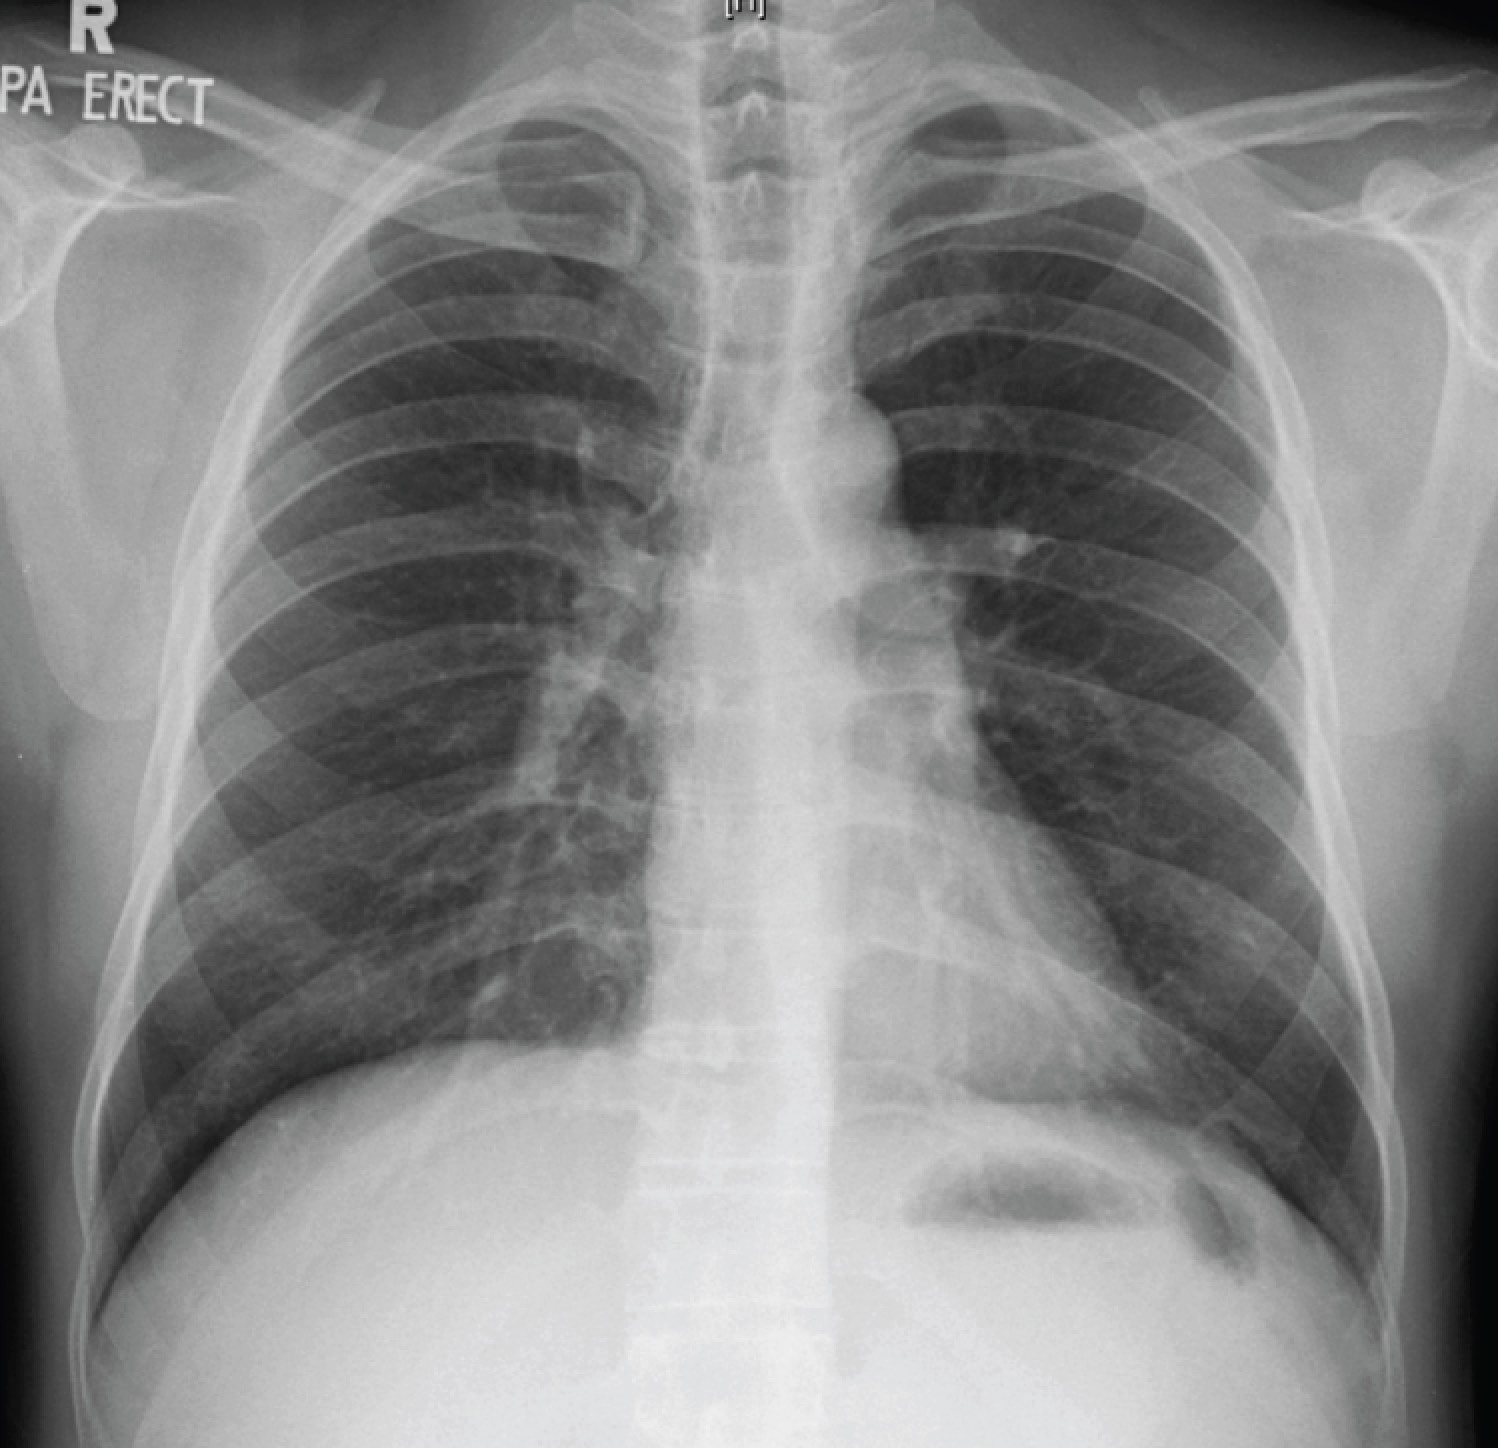

Clinical examination was unremarkable except for a drop in SpO2 to 92% after a brisk walk around the hospital room. The chest X-ray showed faint miliary shadows in both lung fields (the CXR image is provided below, but unfortunately the resolution is insufficient to permit visualisation of the abnormalities), which was confirmed on CT thorax.